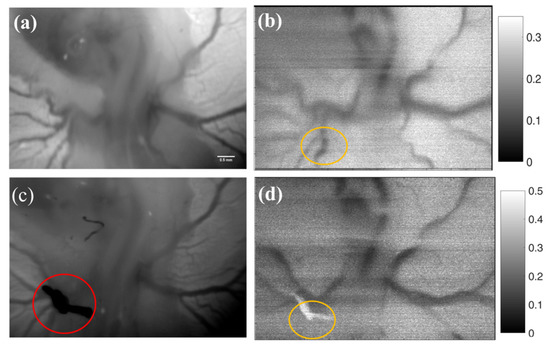

3.4. Imaging Blood Flow Changes during Vascular Clipping Using LS-SSCI